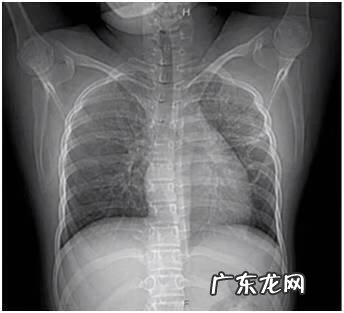

治疗一周后明显好转:

文章插图